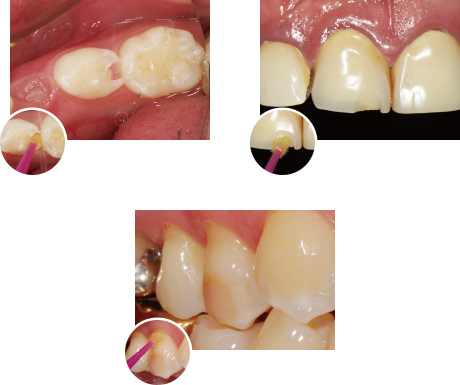

塗布後の待ち時間 「0秒」の簡便性

ボンディング材塗布後、待ち時間なしで乾燥、光照射へとスピーディにおこなえ、特に唾液の多い下顎臼歯部や小児、高齢者の症例等にもストレスなくコンポジットレジン修復がおこなえます。

基本ステップ(コンポジットレジン修復)

象牙質レジンコーティング法ステップ